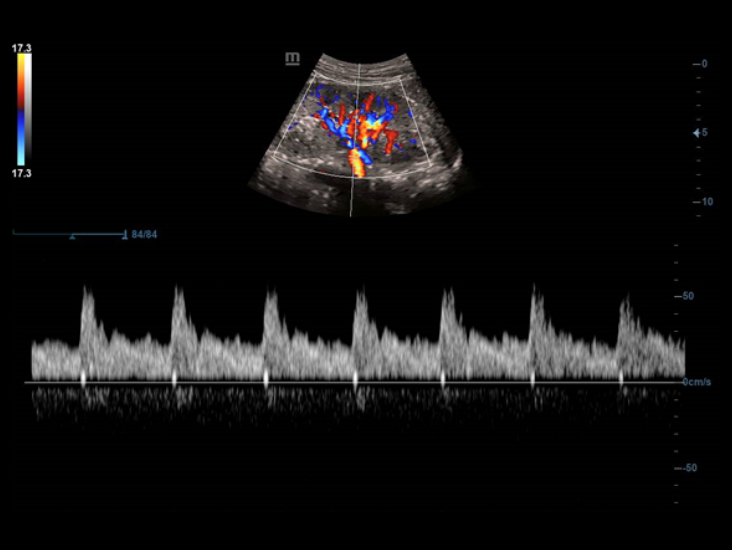

Volle Palette der Anwendungstools: Genauigkeitsgarantie mit bequemem iTouch

DC-40 mit Full HD bietet viele Tools zur bequemen Maximierung der diagnostischen Genauigkeit. Das DC-40 mit Full HD deckt die allgemeine Bildgebung, die Obstretik/Gyn?kologie sowie die Kardiologie ab und bietet damit eine Komplettl?sung f├╝r die wichtigsten klinischen Bereiche, mit vereinfachtem Workflow f├╝r mehr Effizienz.